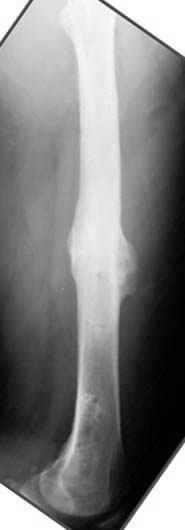

Если, например, доводится лечить больных с псевдартрозами шейки бедра, то надобность есть, и приходится. См. приложение.

Несколько снимков из моей коллекции, чтобы разьяснить, почему мы до сих пор делаем различные варианты остеотомии.

На рисунке N1 предоперационный план лечения ложного сустава шейки бедра- линия ложного сустава, угол и направление введения импланта, клиновидная остеотомия в градусах и миллиметрах, второй снимок после коррекции, расчет, на сколько удлиняется конечность и размеры импланта;

N3 рисунок окончательный снимок, после операции моя рентгенограмма должен выглядеть примерно как эта картина. На N4 снимке клин перед удалением; N5 послеоперации 3 нед.; N6 окончательная рентгенограмма.

пластическая модель; и коррекция бедра аппаратом Илизарова.